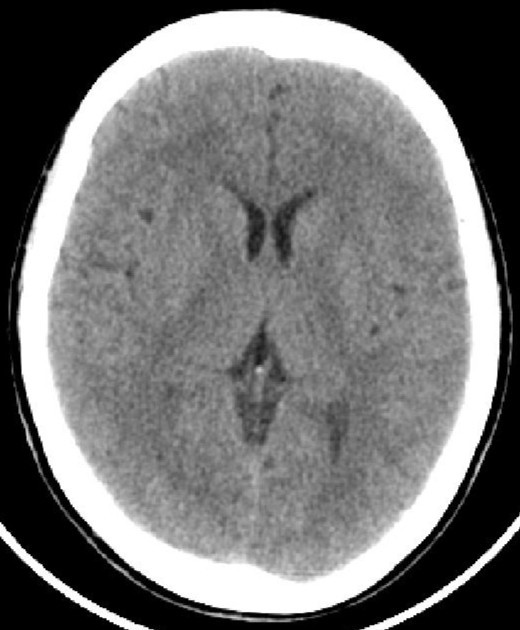

因為腦脊液的分泌、或循環(huán)、或吸收過程中出現(xiàn)障礙,則會產(chǎn)生腦積水。腦積水致腦脊液的容積增大,導致腦血流量及腦組織受壓并容積減少。臨床分類多樣:嬰幼兒腦積水和成人腦積水;高壓性腦積水和常壓性腦積水;腦室內(nèi)腦積水和腦外腦積水;癥狀性腦積水和無癥狀性腦積水;進行性腦積水和靜止性腦積水。比較常用的是按病因分類:交通性腦積水和阻塞性腦積水。其中交通性腦積水病因:腦脊液吸收功能障礙、蛛網(wǎng)膜顆粒發(fā)育不良、腦脊液成份改變或濃縮及腦脊液分泌過多;阻塞性腦積水病因:中腦水管狹窄或閉塞、Dandy-Walker綜合征、小腦扁桃體下疝畸形、炎癥或出血、顱內(nèi)占位性病變等。臨床癥狀:嬰幼兒有發(fā)育延遲、頭顱增大、行走障礙等;成人可有神志及精神變差、記憶力下降、頭痛頭暈、行走困難或二便失控等。頭顱CTMR可以明確診斷及辨別病因。治療主要以手術(shù)治療為主。絕大多數(shù)患者愈合良好。(神經(jīng)外科 龍青山)

正常頭顱CT          頭顱CT示腦積水